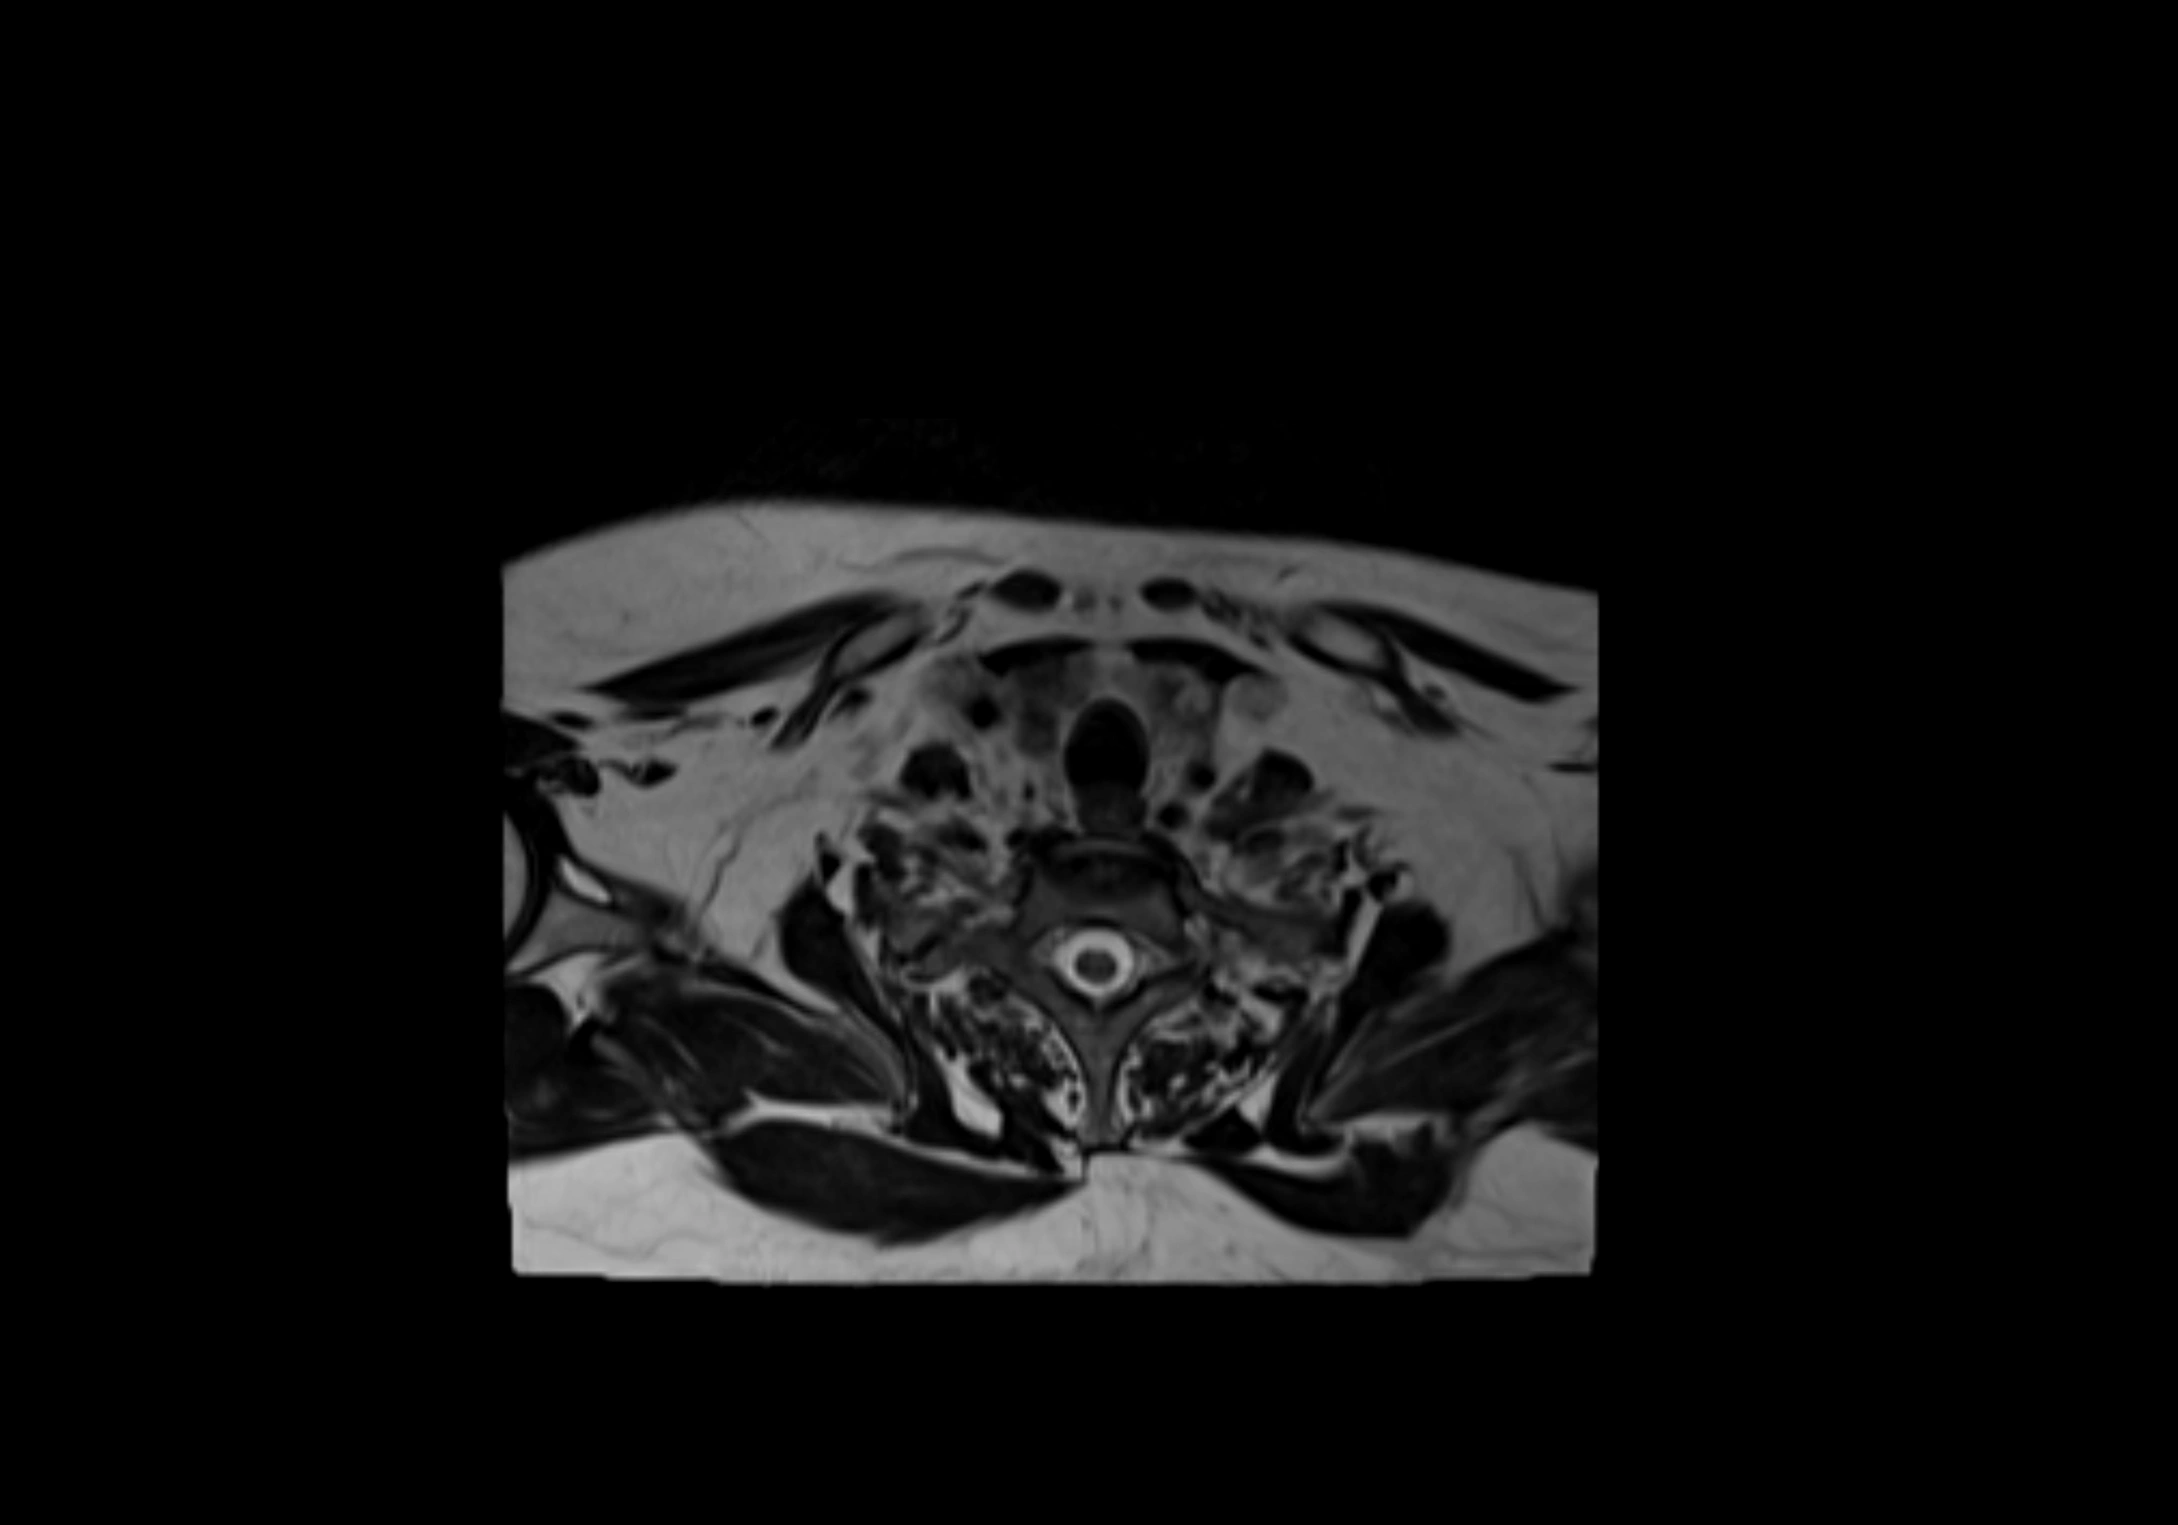

MRI Appearance

T2-weighted images:

• Nodes show intermediate signal, with surrounding fat bright

• Useful for detecting edema, inflammation, or infiltration

• Fatty hilum may appear slightly hyperintense relative to cortex

MRI images

image